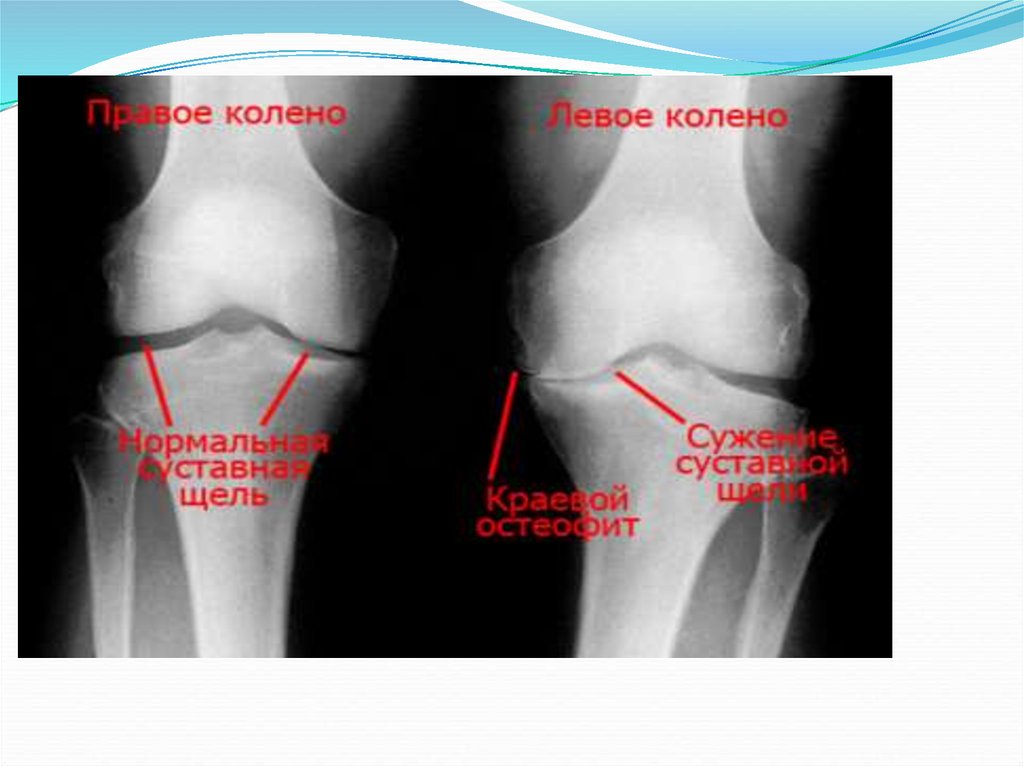

Артроз коленного сустава

Нормальная рентген-анатомия коленного сустава